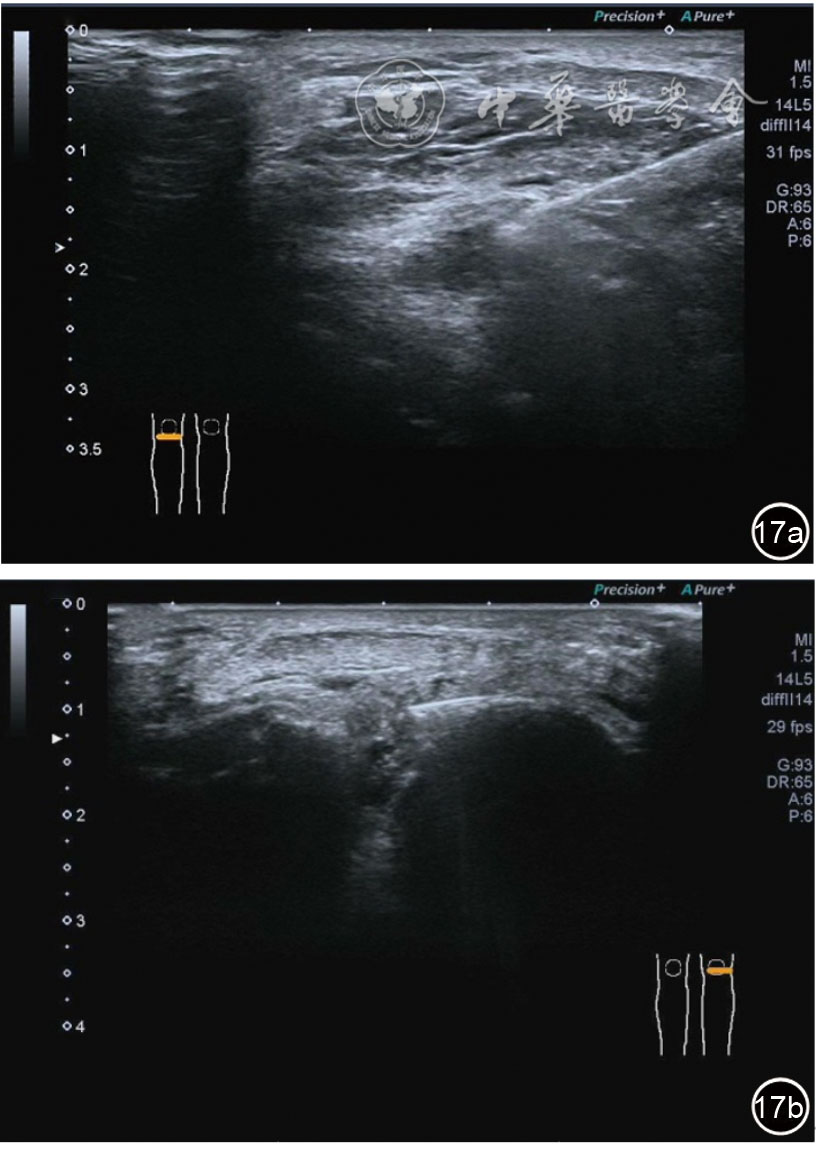

2.膝关节静态结构治疗。动力平衡失调后,继发静态结构变化,出现内外侧副韧带、交叉韧带、脂肪垫、半月板等结构变化。这里介绍半月板与交叉韧带的处理。(1)膝关节静态结构半月板治疗。在膝关节骨关节炎中主要是突出和损伤。突出主要发生于膝内翻引起的内侧半月板突出,引起内侧副韧带的张力增高。内侧半月板与内侧副韧带相连,是引起膝关节内侧疼痛的主要原因之一。治疗主要是针刀剥离松解,部分损伤可行PRP注射。①半月板突出针刀剥离松解治疗。针刀治疗主要是松解和减压,缓解疼痛,不能复位。以内侧半月板突出治疗为例。患者平卧位,髋轻度外展外旋,膝关节屈曲30°,膝下垫一软枕。选用10 MHz超声探头,穿刺区域常规消毒,探头涂抹耦合剂后套入无菌手套碘伏消毒或使用无菌耦合剂。将探头置于患者皮肤表面,内侧关节间隙长轴扫查,找到半月板突出最高点,用25G针头,抽吸1%利多卡因3 ml逐层麻醉直到半月板。选用直径1 mm的Ⅰ型2号针刀从头侧向足侧方向在内侧副韧带与半月板之间,以及半月板内部进行剥离松解3~5刀拔出针刀(图13),局部压迫5分钟,无菌敷料覆盖。②半月板损伤PRP注射治疗。半月板损伤主要表现为髌下痛,伸膝加重,查体在髌下髌韧带与侧副韧带之间,沿关节间隙有固定或局限性压痛,伸膝过程中尤为明显。MRI可示半月板断裂、损伤。如果出现绞索,严重影响功能需手术治疗。半月板损伤治疗,以注射PRP修复为主。以内侧半月板后角损伤为例。患者俯卧位,治疗前准备同半月板突出针刀剥离松解治疗。选用25G注射针头,抽取1%利多卡因2 ml局部麻醉后,制取1.5 ml PRP,穿刺到达半月板撕裂处注射,注射完毕后出针(图14),局部压迫2分钟,无菌敷料覆盖。(2)膝关节静态结构交叉韧带治疗。膝关节骨关节炎交叉韧带损伤多为部分损伤,治疗早期主要为药物或PRP注射,效果不佳时针刀做止点松解。①后交叉韧带损伤药物注射治疗。主要治疗韧带肿胀、无明显断裂患者。患者俯卧位,膝关节伸直位。一般选用10 MHz超声探头,治疗前准备同半月板突出针刀剥离松解治疗。将探头置于患者皮肤表面,后交叉韧带长轴扫查,找到胫骨止点,选用22G长针头,抽吸1%利多卡因3 ml+曲安奈德10 mg,从头侧向足侧方向穿刺到后交叉韧带胫骨止点部位的韧带表面进行注射,注射结束拔出针头(图15),局部压迫2分钟,无菌敷料覆盖。②前交叉韧带损伤PRP注射治疗。患者仰卧位,膝关节伸直。选用10 MHz超声探头,治疗前准备同半月板突出针刀剥离松解治疗。将探头置于患者皮肤表面,短轴扫查,找到前交叉韧带胫骨止点,选用25G针头,抽吸1%利多卡因3 ml逐层麻醉直到韧带止点部位,制备PRP 3 ml注射到前交叉韧带显露部位,注射结束拔出针头(图16),局部压迫2分钟,无菌敷料覆盖。③前交叉韧带损伤针刀剥离松解治疗。体位与治疗前准备同前交叉韧带损伤PRP注射治疗。短轴扫查找到前交叉韧带胫骨止点,选用25G针头,抽吸1%利多卡因3 ml逐层麻醉直到韧带止点部位,选用直径0.6 mm的Ⅰ型2号针刀从外侧向内侧于前交叉韧带胫骨止点部位剥离松解3~5刀拔出针刀(图17),局部压迫5分钟,无菌敷料覆盖。

图17 超声引导下前交叉韧带损伤针刀剥离松解治疗